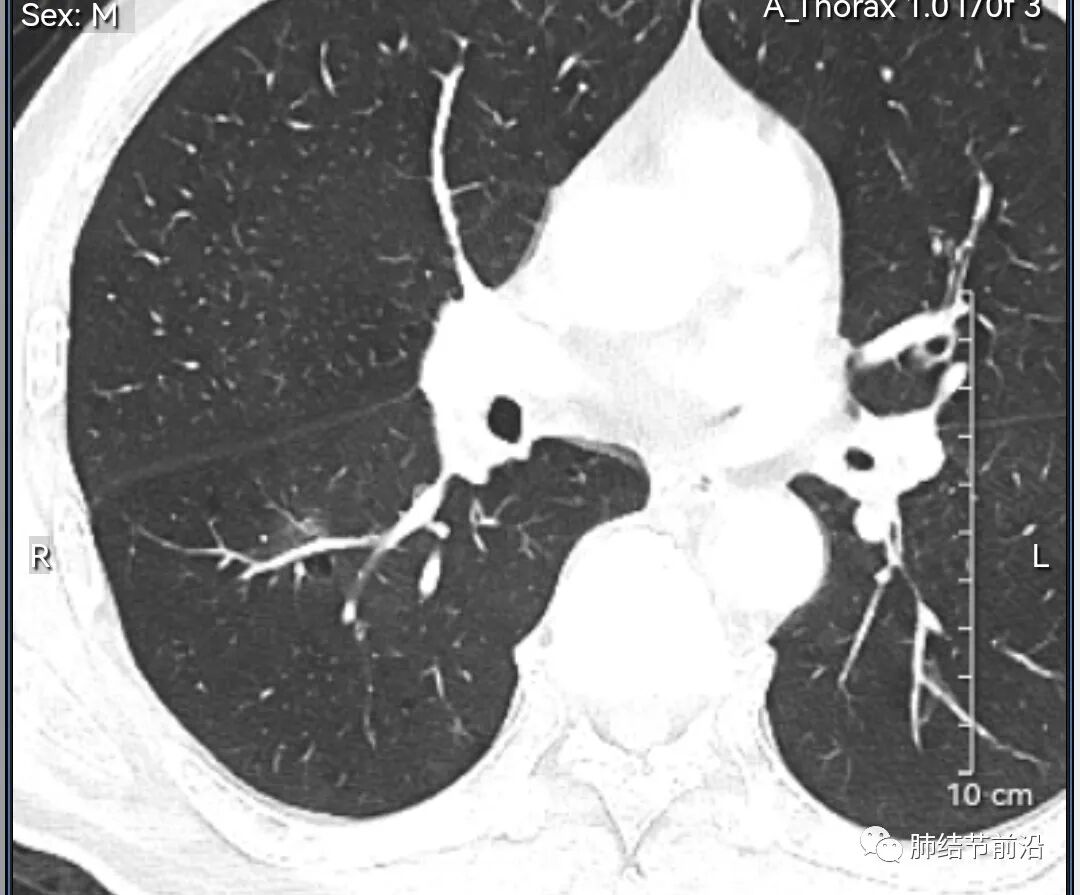

男性,67岁,重度吸烟史。CT发现右下肺囊腔。来看一下这个CT的特点:

该囊腔形态非常有特点,和常见的圆形肺大泡有很大的区别。

1.囊腔中央实性成分,周围有磨玻璃影。

2.囊腔中央有血管。

3.囊腔外周有分叶形态。

4.囊腔有胸膜牵拉。

出现这几种形态,CT可以确认恶性的腺癌。这个囊腔形成的机制,为肿瘤实性成分堵塞细支气管形成活瓣,肺泡内压力增高破裂行成,因此肺内血管成分保留。由于肺泡压力增高,而呈分叶状。另外,也有肿瘤的胸膜牵拉这一特点。

囊腔周围磨玻璃+囊腔中央血管为特征性表现。如果持续存在,几乎可以100%确认为早期肺腺癌。